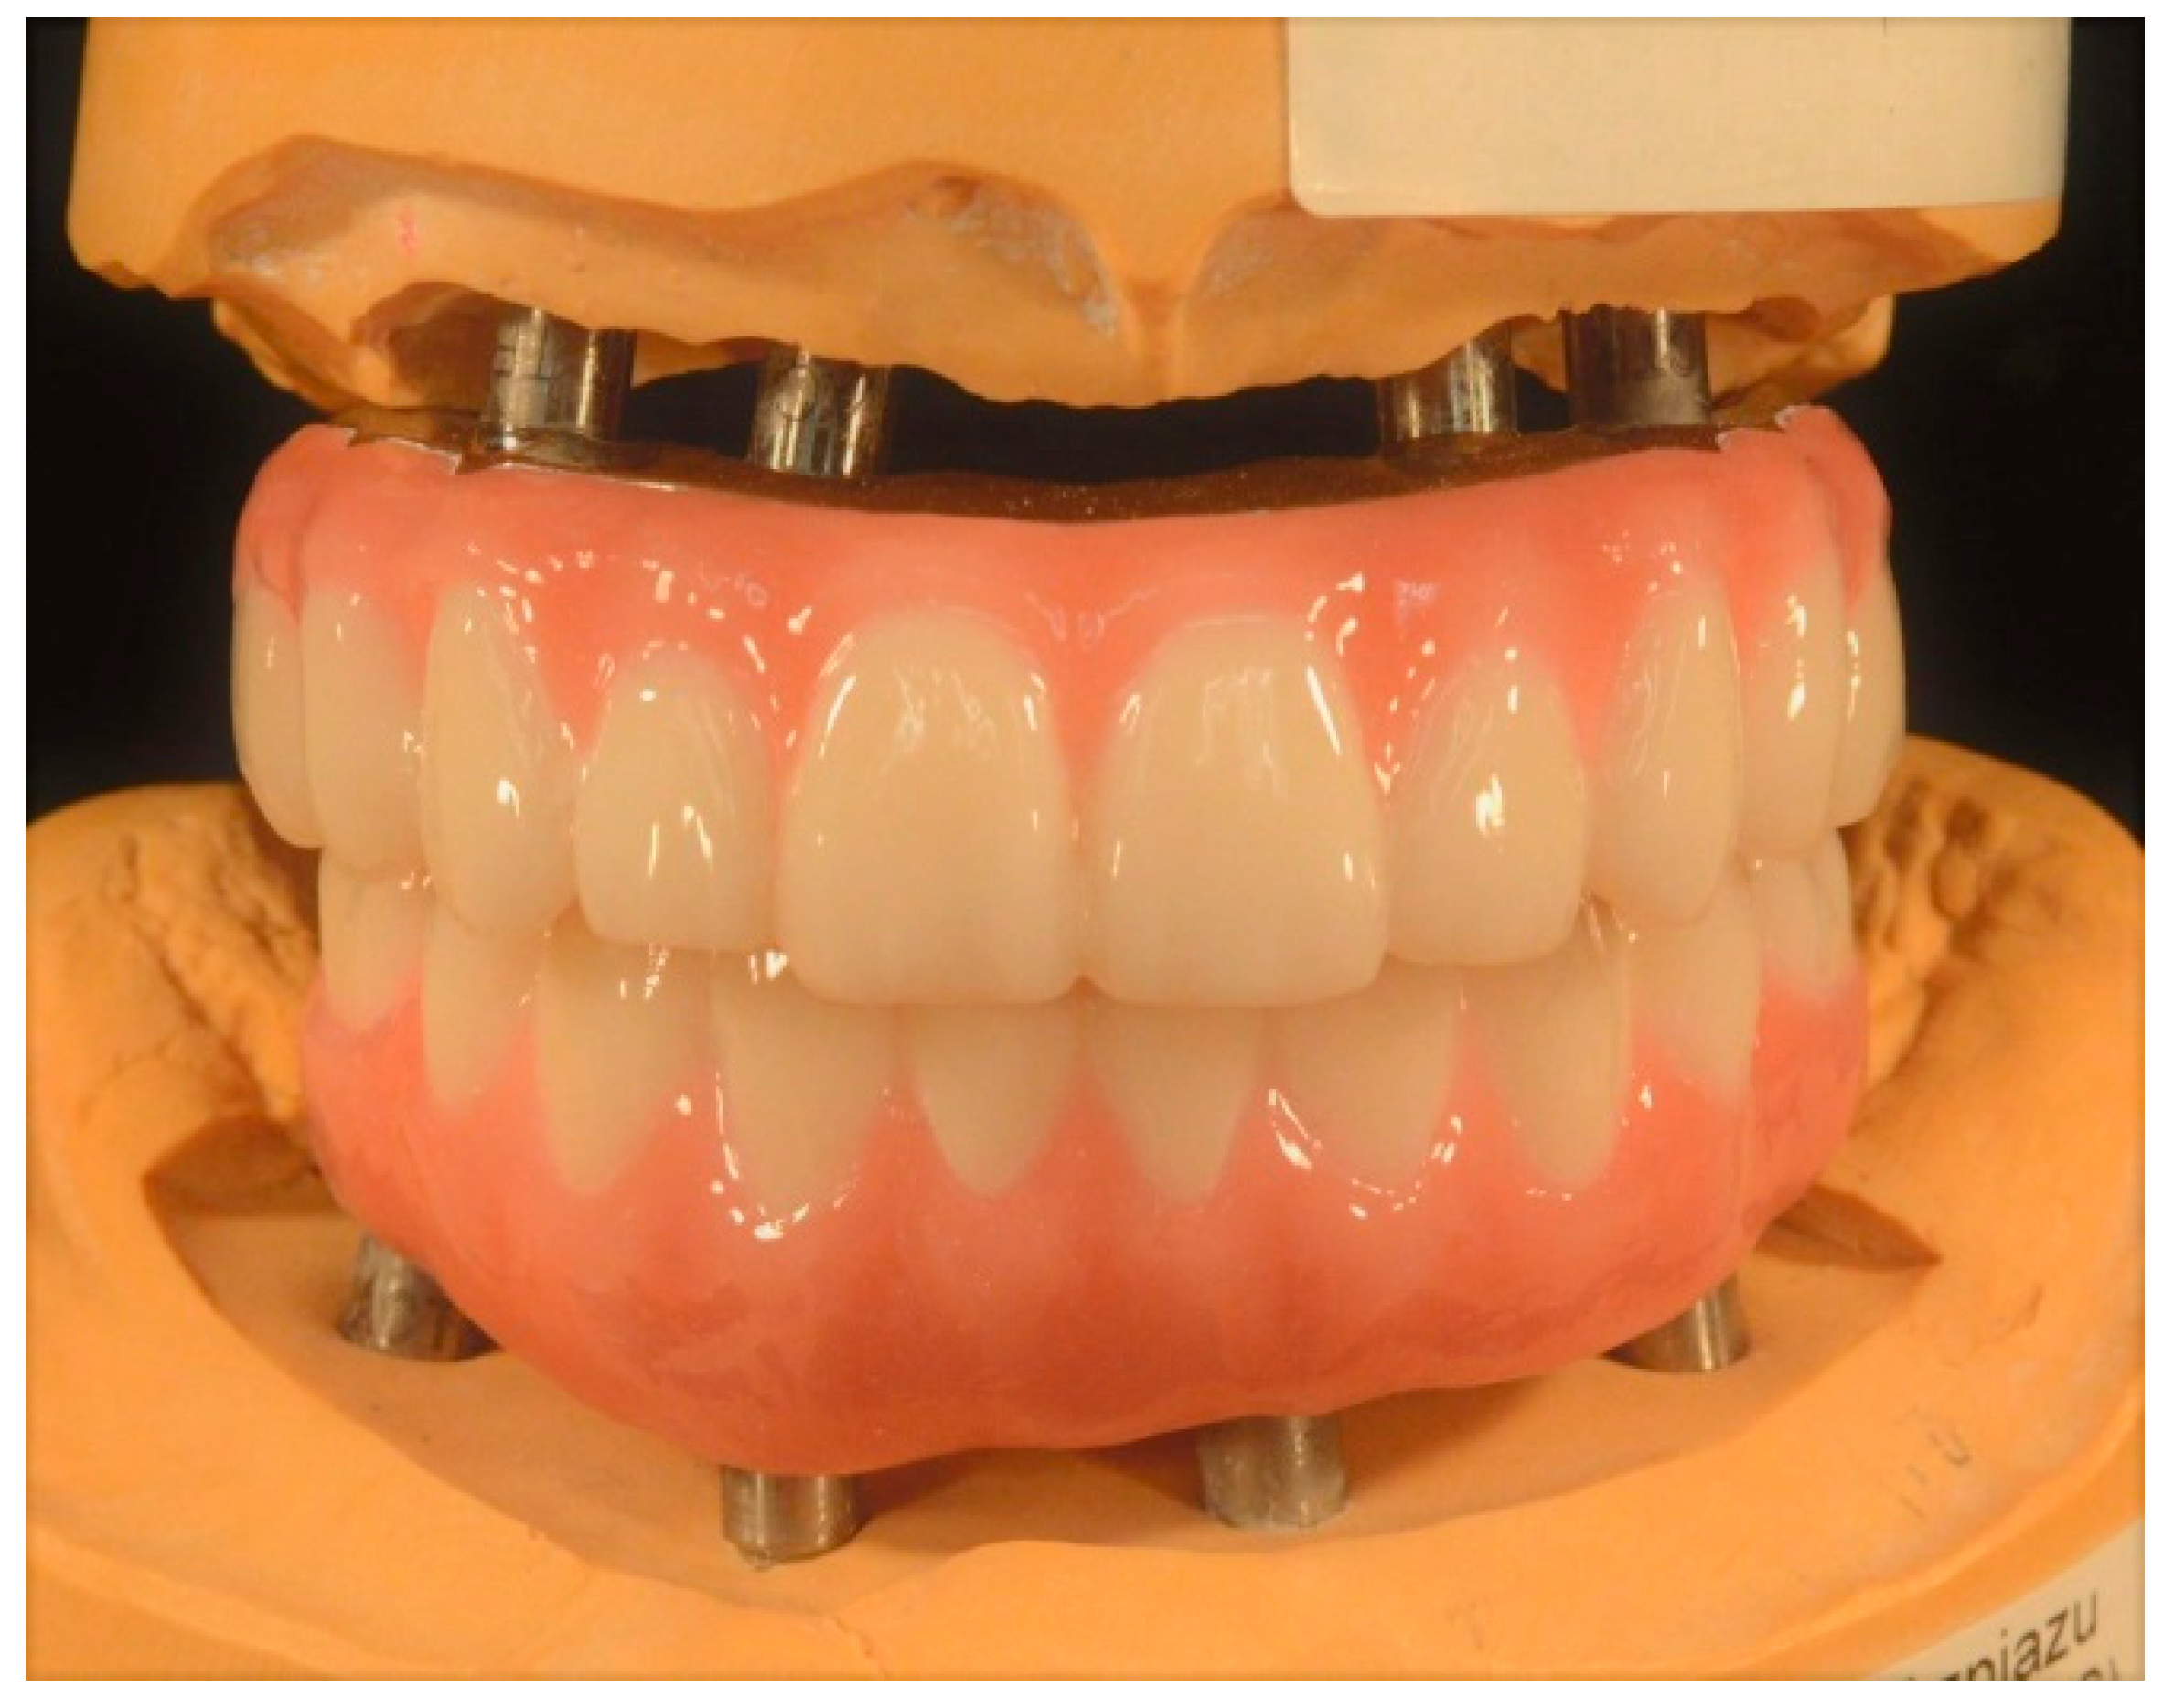

Full-Mouth Rehabilitation of a Patient with Sjogren’s Syndrome with Maxillary Titanium-Zirconia and Mandibular Monolithic Zirconia Implant Prostheses Fabricated with CAD/CAM Technology: A Clinical Report

2. Materials and Methods

3. Results